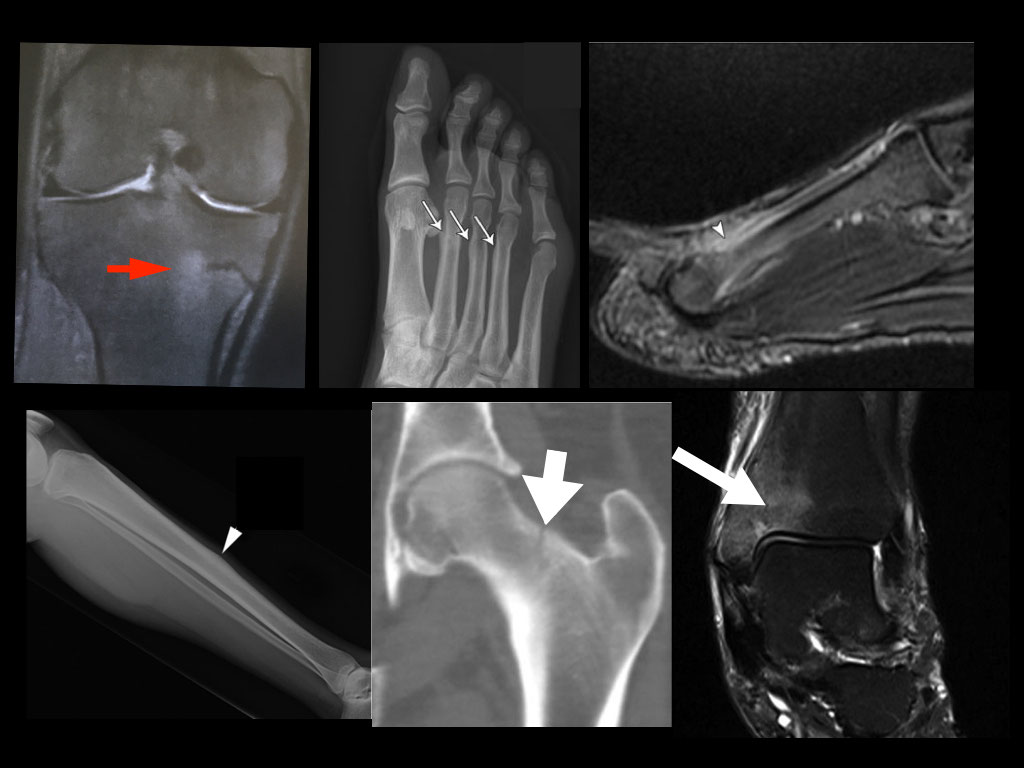

From www.nejm.org

Fatigue Fracture of the Pelvis and the Lower Extremity NEJM Fatigue Fracture Of Vertebra Learn about the different types of spinal fractures, such as compression, burst and chance fractures, and how they affect your back. Fatigue sacral fractures (fsfs) are rare and often misdiagnosed. Fatigue fracture of human lumbar vertebrae under cyclic axial compressive load has been investigated in vitro for load magnitudes. Fatigue fracture of human lumbar vertebrae under cyclic axial compressive load. Fatigue Fracture Of Vertebra.

Fatigue Fracture of the Pelvis and the Lower Extremity NEJM Fatigue Fracture Of Vertebra Fatigue fracture of human lumbar vertebrae under cyclic axial compressive load has been investigated in vitro for load magnitudes between 20% and 70%. Fatigue fracture of human lumbar vertebrae under cyclic axial compressive load has been investigated in vitro for load magnitudes between 20% and 70%. Fatigue fracture of human lumbar vertebrae under cyclic axial compressive load is investigated between. Fatigue Fracture Of Vertebra.